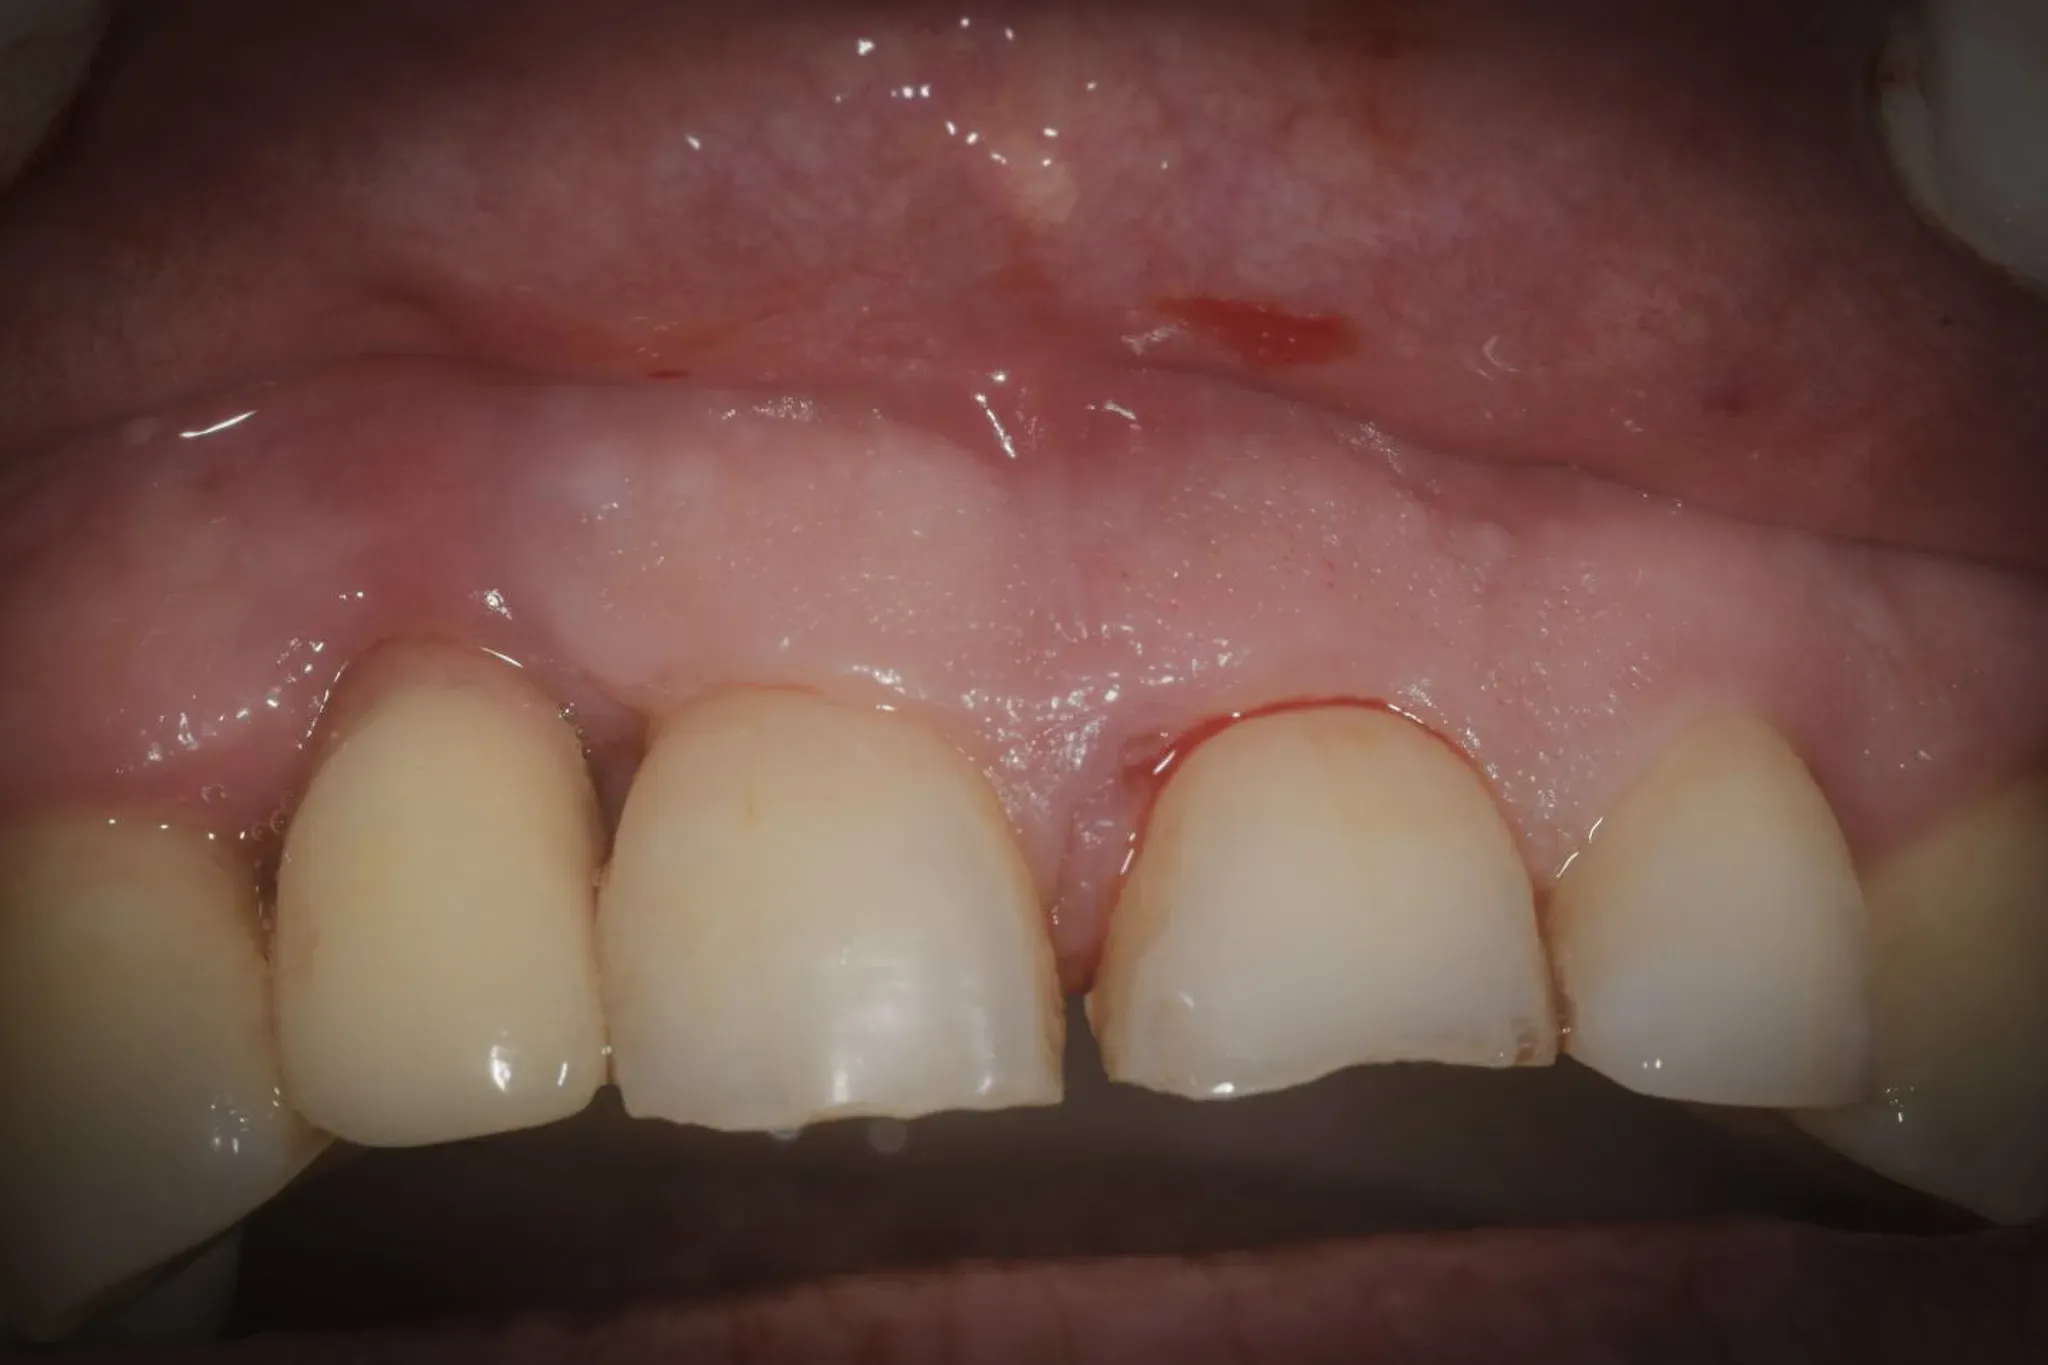

The clinical picture

Implant at position 1.2. Advanced peri-implantitis: crater-shaped defect, buccal cortical dehiscence, bone loss of approximately 40% of implant length. The adjacent teeth showed advanced periodontal lesions. The challenge was not just decontaminating the implant — it was treating the entire sector in a single surgical session without compromising the regenerative potential of the adjacent teeth.